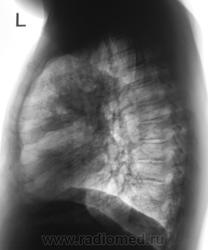

Динамика через 1,5 года.

На перый снимках двусторонняя инфильтрация (пневмония?), на последних похоже на формирующийся абсцесс в левом легком.

На первых снимках, ретроспективно, смутило повышение прозрачности левого легочного поля.

Были произведены томограммы в прямой проекции.

Были произведены томограммы в боковой проекции.

#18, рис. 2. - четкие признаки нарушения бронхиальной проходимости (смещение тени средостения в сторону поражения, левый купол диафрагмы выше правого, повышение воздушности правого легкого). Пока мнение мое остается прежним, однако не нравится окружающий фон (очаговость?). Дело за другими методами исследования. Можно поискать и палочки Коха, но локализация не очень подходит. Хотя, на сайте простых клинических наблюдений не бывает Жду.